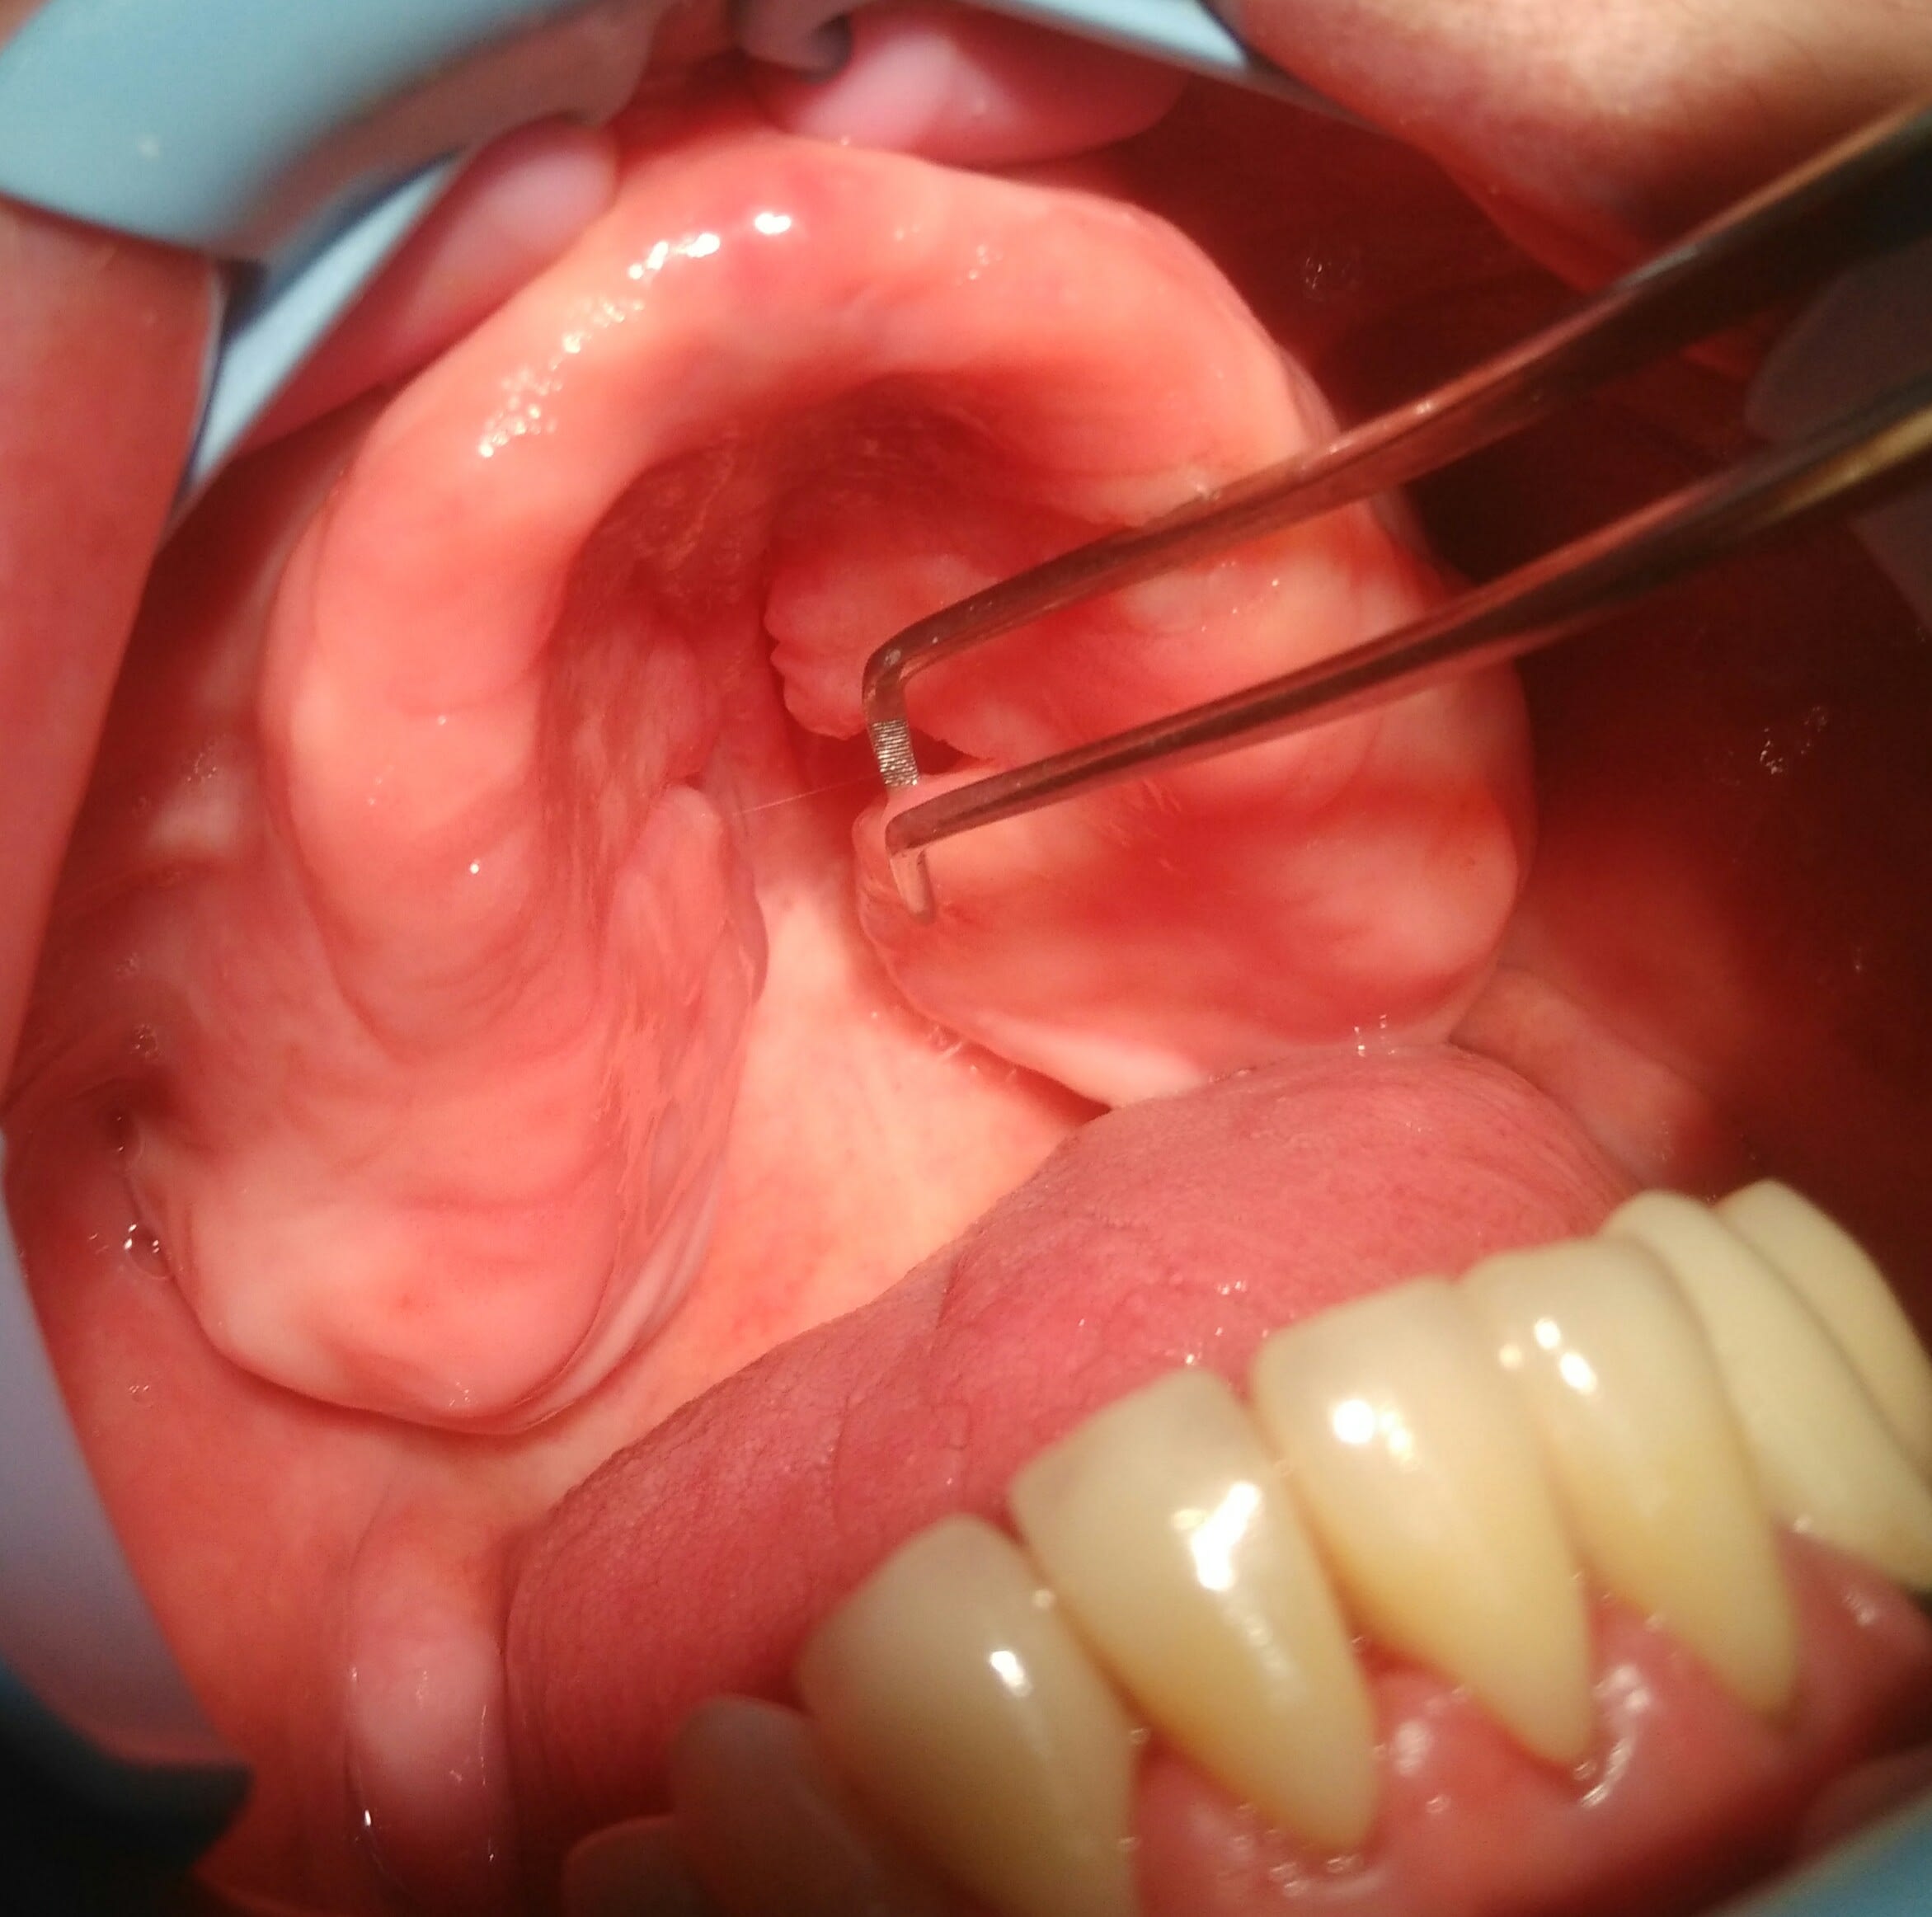

fait aujourd'hui desole pour la qualité des photos plus de piles sur le flash annulaire

critiques bienvenues...(c'est vrai)

Sous la prothèse, hyperplasie gingivale bilatérale palatine.

Y-a-t-il une alternative à la chirurgie?

Img 20170125 090002 ps48gf - Eugenol